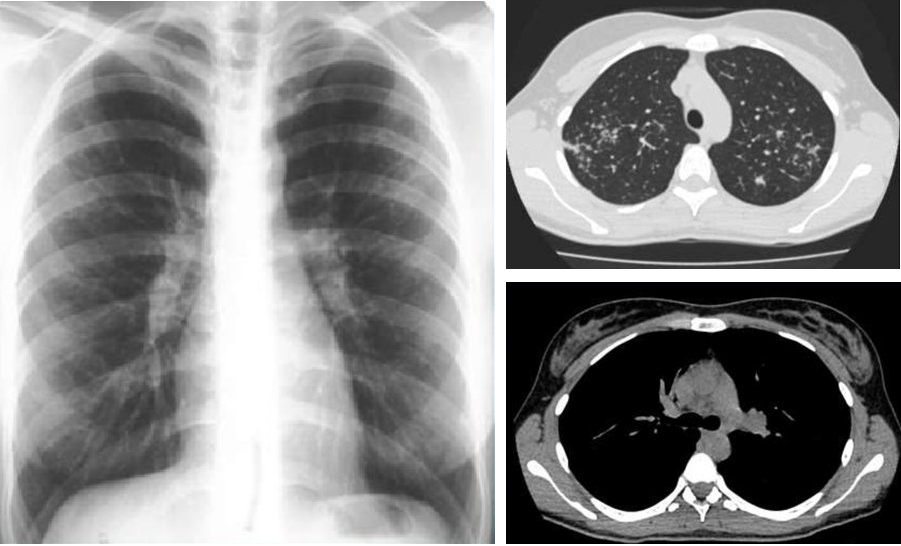

В первую очередь необходимо провести визуализацию грудной клетки, чтобы обнаружить очаги воспаления и увеличенные внутригрудные лимфатические узлы. Затем нужны анализы крови, выделяемой мокроты, данные спирометрии - в том числе чтобы исключить другие заболевания с похожими симптомами. Возможно потребуется биопсия: ведь гранулёмы легко различимы при микроскопическом исследовании.